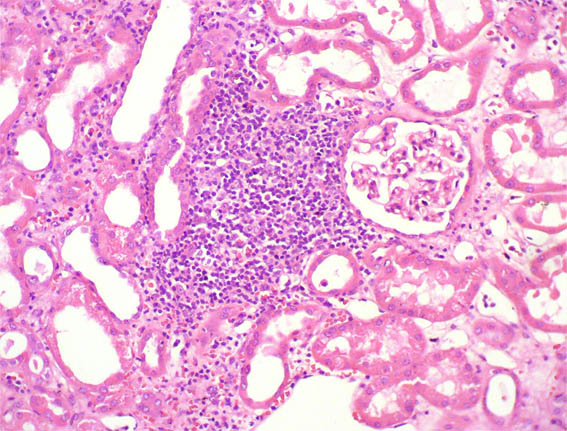

Figure 2.

H&E, X100.